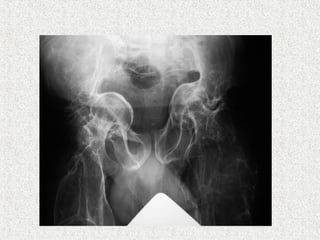

ļ‚ž Acetabular protrusion

ļ‚ž Radiograph

ļ‚” Generalised osteopenia

ļ‚” Thinning of long bone

ļ‚” # in various stages of healing

ļ‚” Vertebral compression

ļ‚” Spinal deformity

ļ‚” Skull enlarged

ļ‚” Wormian bones in skull-areas of vicarious

ossification n the calvarium

ļ‚” Widening of metaphysis

ļ‚” Popcorn epiphysis